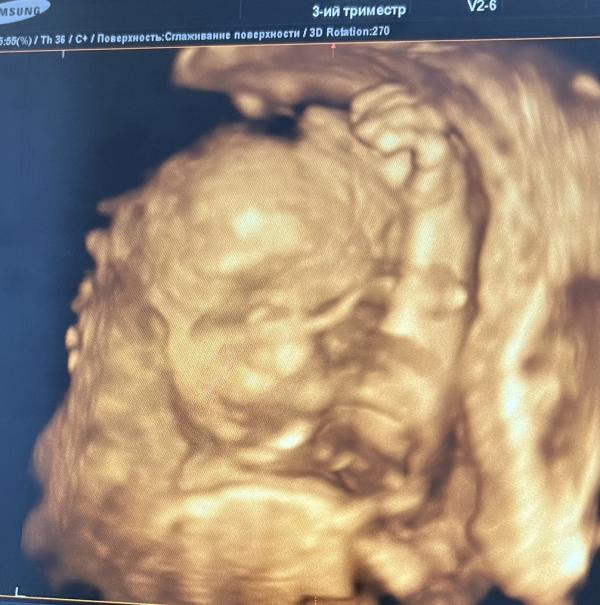

Сегодня прошла 3 скрининг УЗИ и доплер , ровно 30 недель 😍🙏🏻 все хорошо по узи и доплеру но весь маленький ) моя Дюймовочка🥰моя малышка , лежим как хотим 😅 пока лежит тазовое 🙃